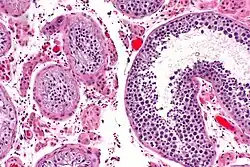

Orchitis

Orchitis, or inflammation of the testicles due to a bacterial or viral infection, can lead to testicular atrophy.[9] Mumps has historically been significantly associated with orchitis and testicular atrophy, but has become rare in countries that have high mumps vaccination rates.[9]